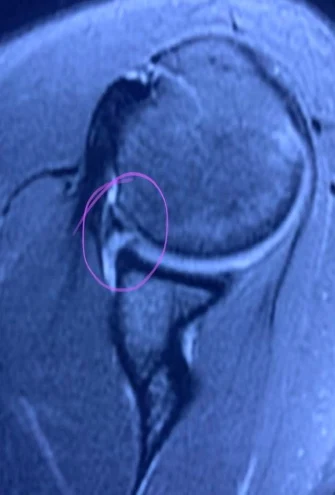

Soft tissue Bankart variedad GLAD, en la inestabilidad del hombro por luxaciones glenohumerales anteriores.

Reinserción artroscopica del rodete glenoideo con Arthrex pushlock* y suture tape* knotless, en portero profesional.

Lesión deportiva frecuente en atletas de alta demanda.

Jointsolutions, expertos en traumatología deportiva. Trece años de artroscopia de alta especialidad en el hombro.